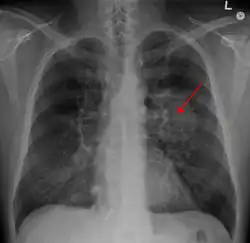

A previously healthy 16-year-old male presented with progressive shortness of breath, cough, and hypoxemia in the setting of several months of daily nicotine and THC-containing e-cigarette use. He had been suffering from a chronic cough and intermittent nausea since he started vaping several months before presentation. His cough worsened 1 week before admission to the hospital, accompanied by vomiting induced by coughing and non-bloody diarrhea. He subsequently developed a fever and was evaluated in an Emergency Department. A chest radiograph showed a right lower lobe pneumonia prompting outpatient treatment with bacterial infection medication (Shah et al., 2020).

Figure 3. X ray of lung cancer

Research on the long-term health effects of the orally-ingested toxicants delivered via aerosolized vapor in e-cigarettes is limited, however, there is rising concern about the health impacts among youth who begin using e-cigarettes at an early age (Williams et al., 2020). Many of the volatile organic compounds found in the saliva and urine samples of e-cigarette users are carcinogenic (Rubinstein et al., 2018). From March 2019 to February 2020, The Centers for Disease Control and Prevention stated that more than 2,807 cases of lung injury associated with e-cigarette use were reported (Rocheleau, 2020). Furthermore, as of 2020, there were 68 deaths associated with e-cigarette use across 29 states in the U.S. (Rocheleau, 2020)